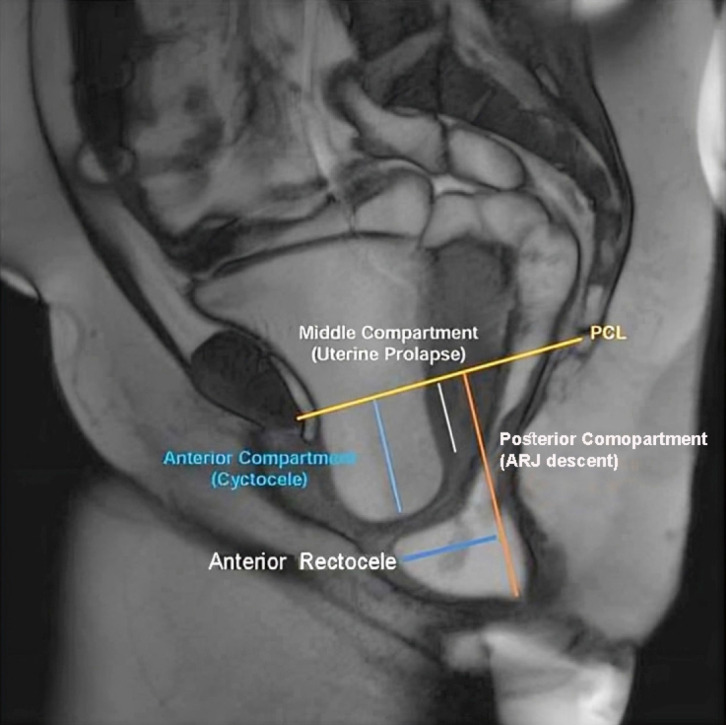

Results: Pelvic floor descent and anorectal junction descent were the most frequent findings, each present in 94.7% of cases. Rectocele was observed in 78.9% of patients, while vaginal or uterine prolapse was seen in 59.4% of females. Less common abnormalities included paradoxical contraction (7%), and there were no cases of sigmoidocele. Functional measurements showed significant differences in pelvic floor dynamics between rest and defecation, particularly in the H-line, M-line, and descent of pelvic organs (P < 0.05).

Conclusion: Pelvic floor descent and anorectal descent were the most common findings in patients suffering from ODS, followed by rectocele. Younger females (< 30 years) were most affected.